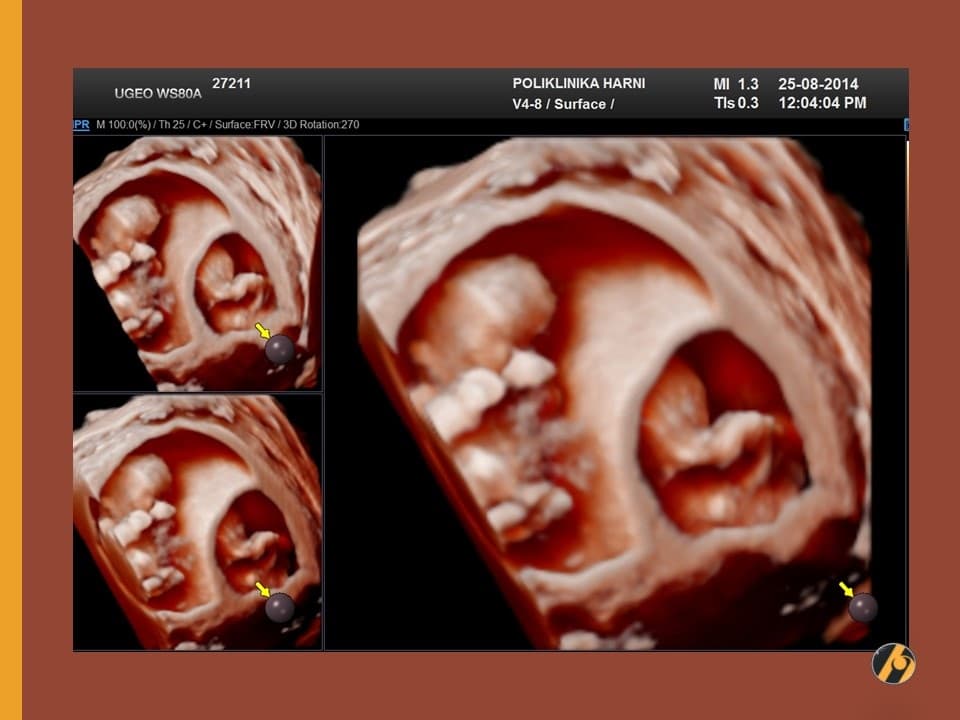

Lice vaše bebe sve je razvijenije. Prepoznaju se korijen nosa, formirani su obrazi, uši su sa strana na vratu prema glavi, a oči su sve bliže jedno drugome. Štitna žlijezda dovršila je svoj razvitak i spremna je za početak stvaranja vlastitih hormona.

Lanugo dlačice otpadaju, a vernix većim dijelom iščezava prije nego što će se beba roditi. Zajedno s lanugo dlačicama pokazuju se obrve, za sada veoma nejasno, čak niče i po koja vlas na glavi. Mišići lica se počinju kontrahirati, pa se nalicu mogu vidjeti grimase i zijevanje. Ispod zatvorenih očnih kapaka počinju se pokretati oči.

Vaša beba dugačka je 8.0 - 11.0 cm, a teška 30 - 60 g.